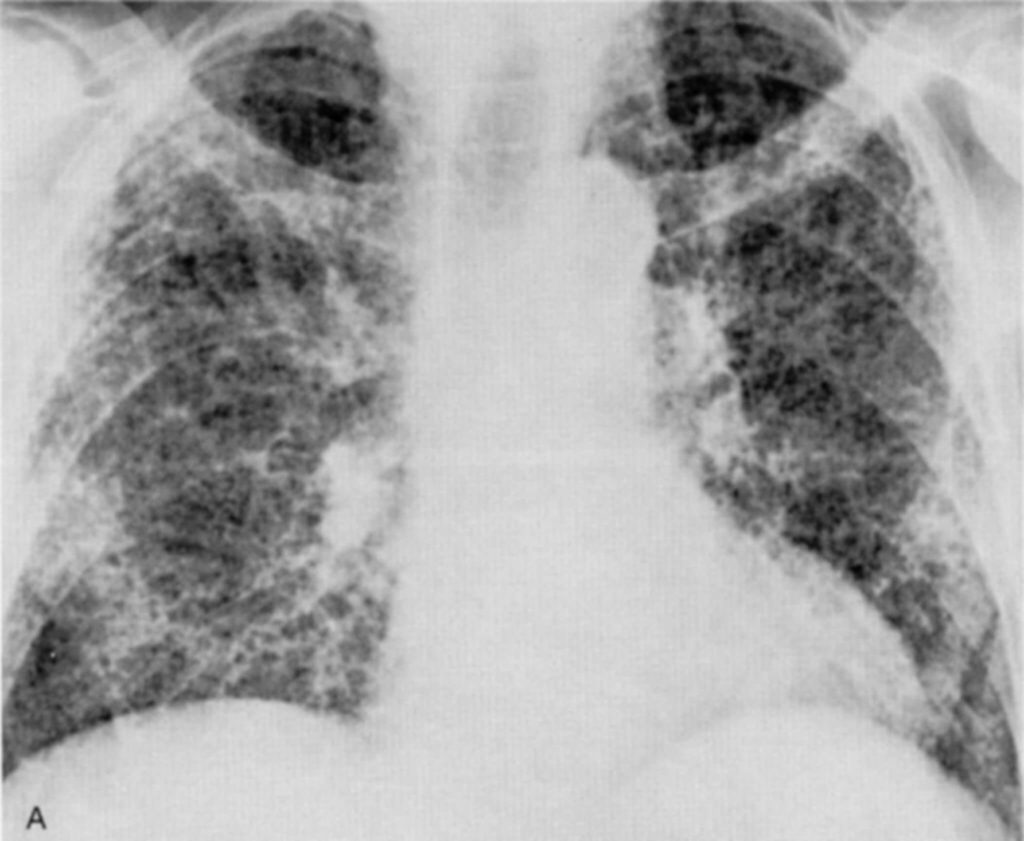

Los hallazgos radiográficos asociados con la fibrosis por radiación pulmonar son distintivos y permiten su identificación. Estos incluyen la obliteración de las marcas pulmonares normales, que se manifiesta como una pérdida de la definición habitual de las estructuras pulmonares en las imágenes. Además, se observa fibrosis intersticial y pleural densa, la cual se traduce en un engrosamiento del tejido intersticial y la pleura, respectivamente. Los volúmenes pulmonares pueden reducirse debido a la pérdida de elasticidad y expansión del tejido pulmonar afectado. También puede observarse una elevación del diafragma, ya que el tejido fibrosado tira de las estructuras circundantes, y una delineación nítida del área irradiada, que resalta el límite entre el tejido sano y el tejido dañado.

Un aspecto relevante de la fibrosis por radiación pulmonar es su aparición no inmediata, sino que puede desarrollarse tras un período intermedio de 6 a 12 meses de aparente bienestar en pacientes que han sufrido neumonía por radiación. Esta secuencia temporal sugiere que la fibrosis pulmonar es una manifestación tardía de la respuesta inflamatoria crónica inducida por la radioterapia. En la mayoría de los pacientes que han recibido un curso completo de radioterapia, la fibrosis pulmonar se desarrolla como una secuela de la exposición a dosis acumulativas de radiación.